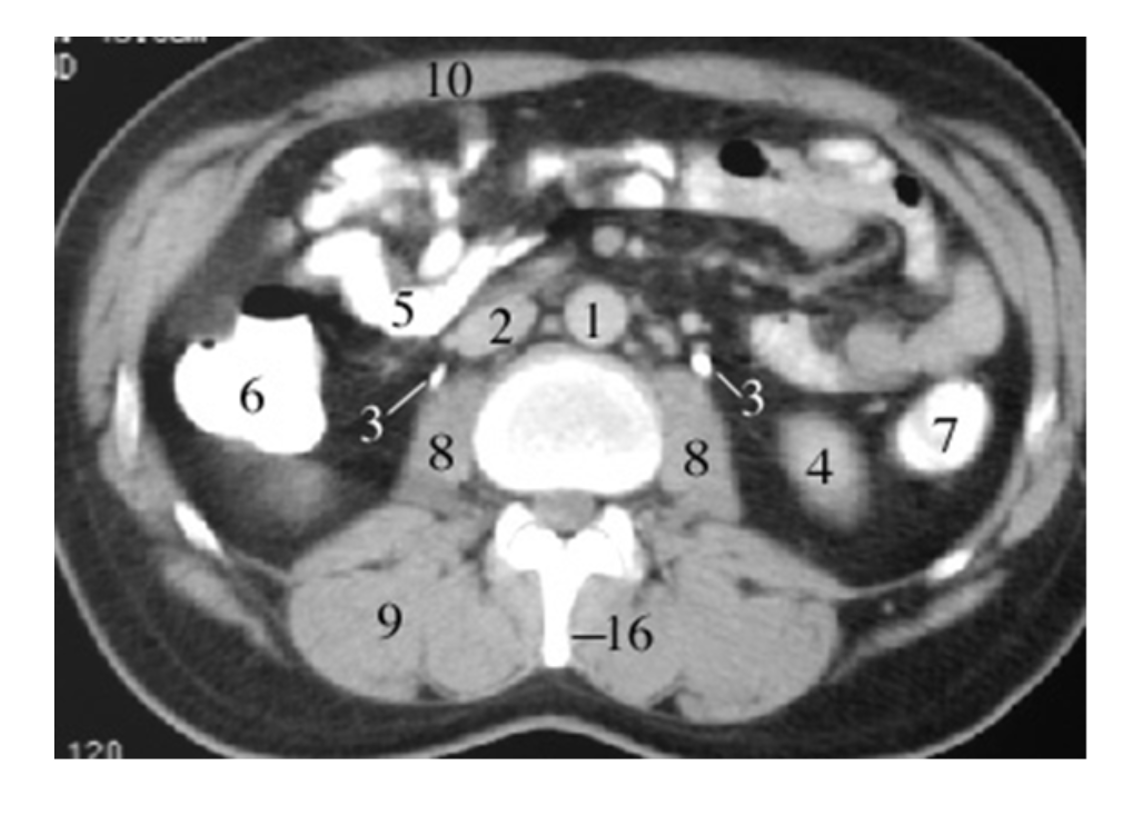

2

aorta

6

ilium

4

left common iliac artery

3

ureters

8

psoas

9

sacram foramen

IV

24

kidney

14

20

small bowel

21

large bowel